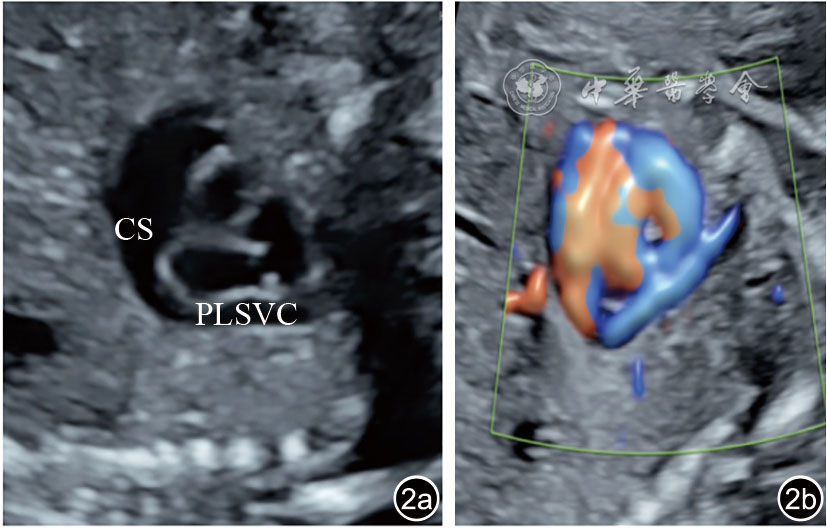

图2 冠状静脉窦旁矢状切面二维超声图像及彩色多普勒血流图像。图示永存左上腔静脉经扩张的冠状静脉窦汇入右心房,图a为二维超声图像,图b为彩色多普勒血流图像 注:CS为冠状静脉窦;PLSVC为永存左上腔静脉